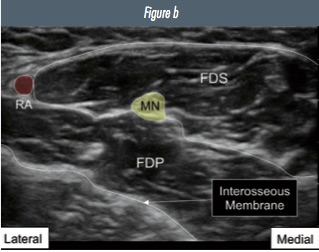

Figure 3: a) ultrasound image of the median nerve and surrounding structures in the mid- forearm b) annotated image (MN=median nerve; FDS= flexor digitorum super cialis; FDP= flexor digitorum profundus).